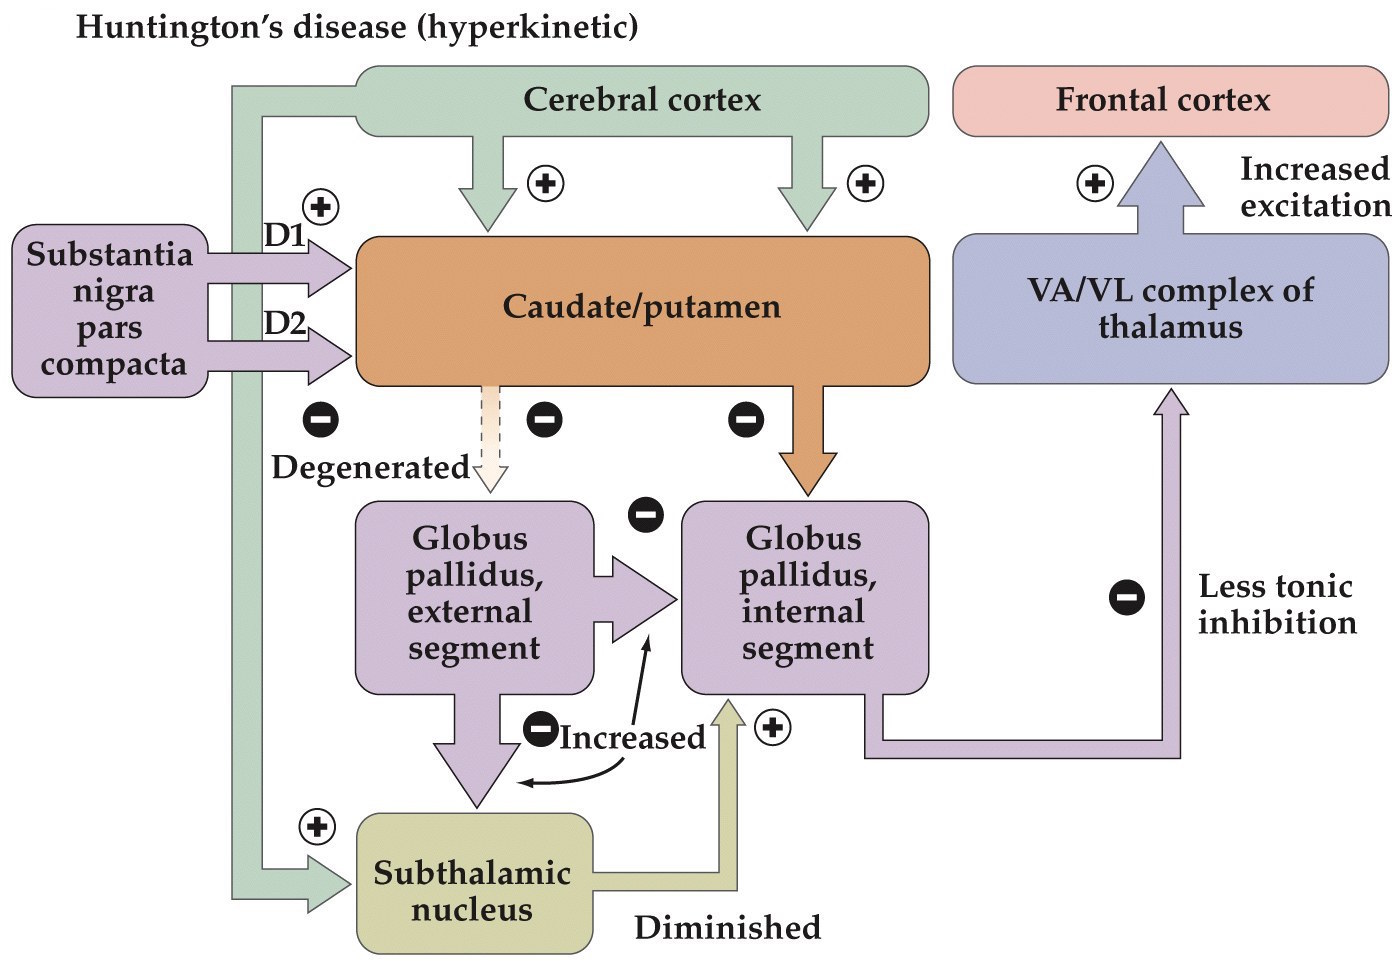

Huntington’s disease

- One of the most common inherited neurological diseases

- Progressive deterioration of the caudate and putamen that project to the GP externa (indirect pathway)

- Leads to a movement disorder consisting of rapid jerky motions with no clear purpose

Huntington’s disease

- Dominantly inherited– strikes around midlife

- Patients develop depression, mood swings, and abnormal movements (striatum)

- Caused by alterations in a single gene that encodes the huntingtin protein

- Huntingtin protein has an expansion of a CAG trinucleotide repeat, resulting in an extended polyglutamine repeat. Leads to aggregation of proteins and cell death

Hypokinetic and hyperkinetic disorders summary

- Parkinson's– hypokinetic disorder. More tonic inhibition of thalamus and decreased excitation of frontal cortex

- Huntington's– hyperkinetic disorder. Less tonic inhibition of thalamus and more excitation of frontal cortex

Note:

Parkinson's– hypokinetic disorder. More tonic inhibition of thalamus and decreased excitation of frontal cortex.

Huntington's– hyperkinetic disorder. Less tonic inhibition of thalamus and more excitation of frontal cortex.